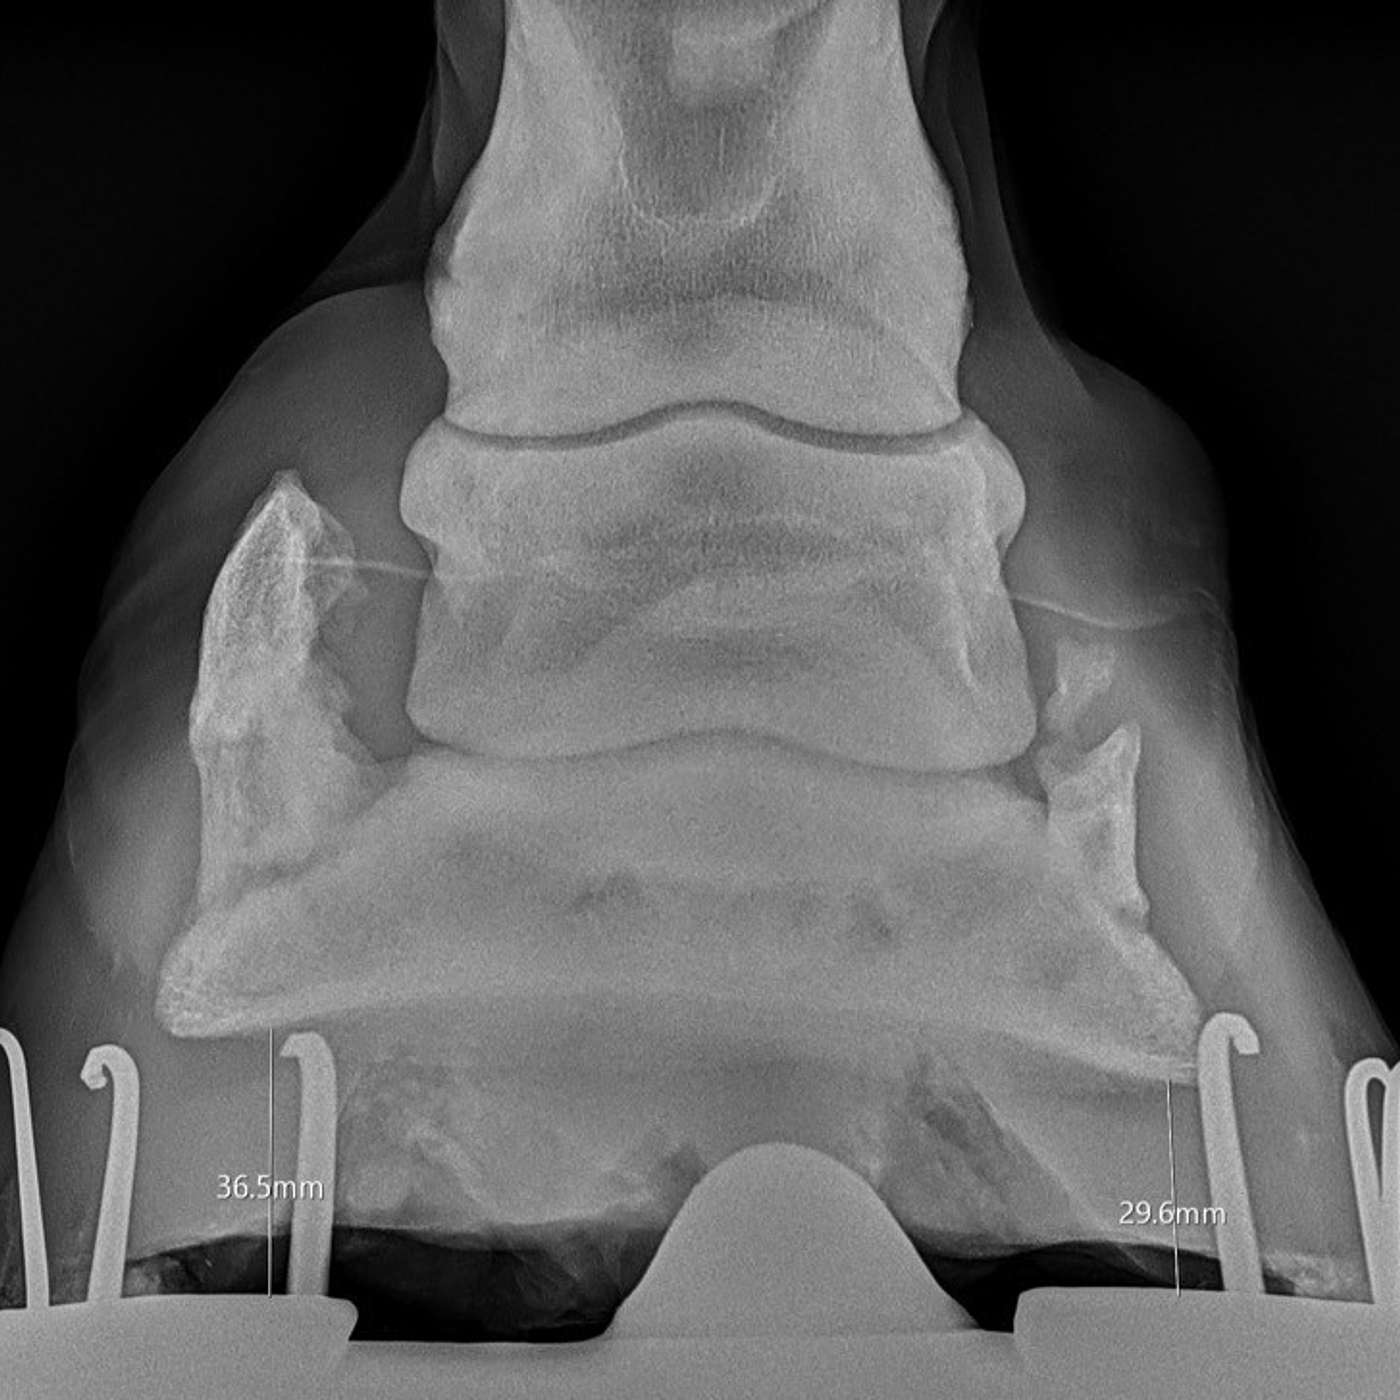

In this episode of The Hoofcare Companion, we dive into the critical role of radiography in assessing equine foot balance. Traditionally, farriers and veterinarians relied on visual and tactile assessment to guide trimming and shoeing, but modern diagnostic imaging has transformed hoof care. Join host Marc Jerram as we explore how radiographs provide deeper insights into hoof alignment, pastern axis, palmar angles, sole depth, and mediolateral balance. We discuss how these measurements influe...